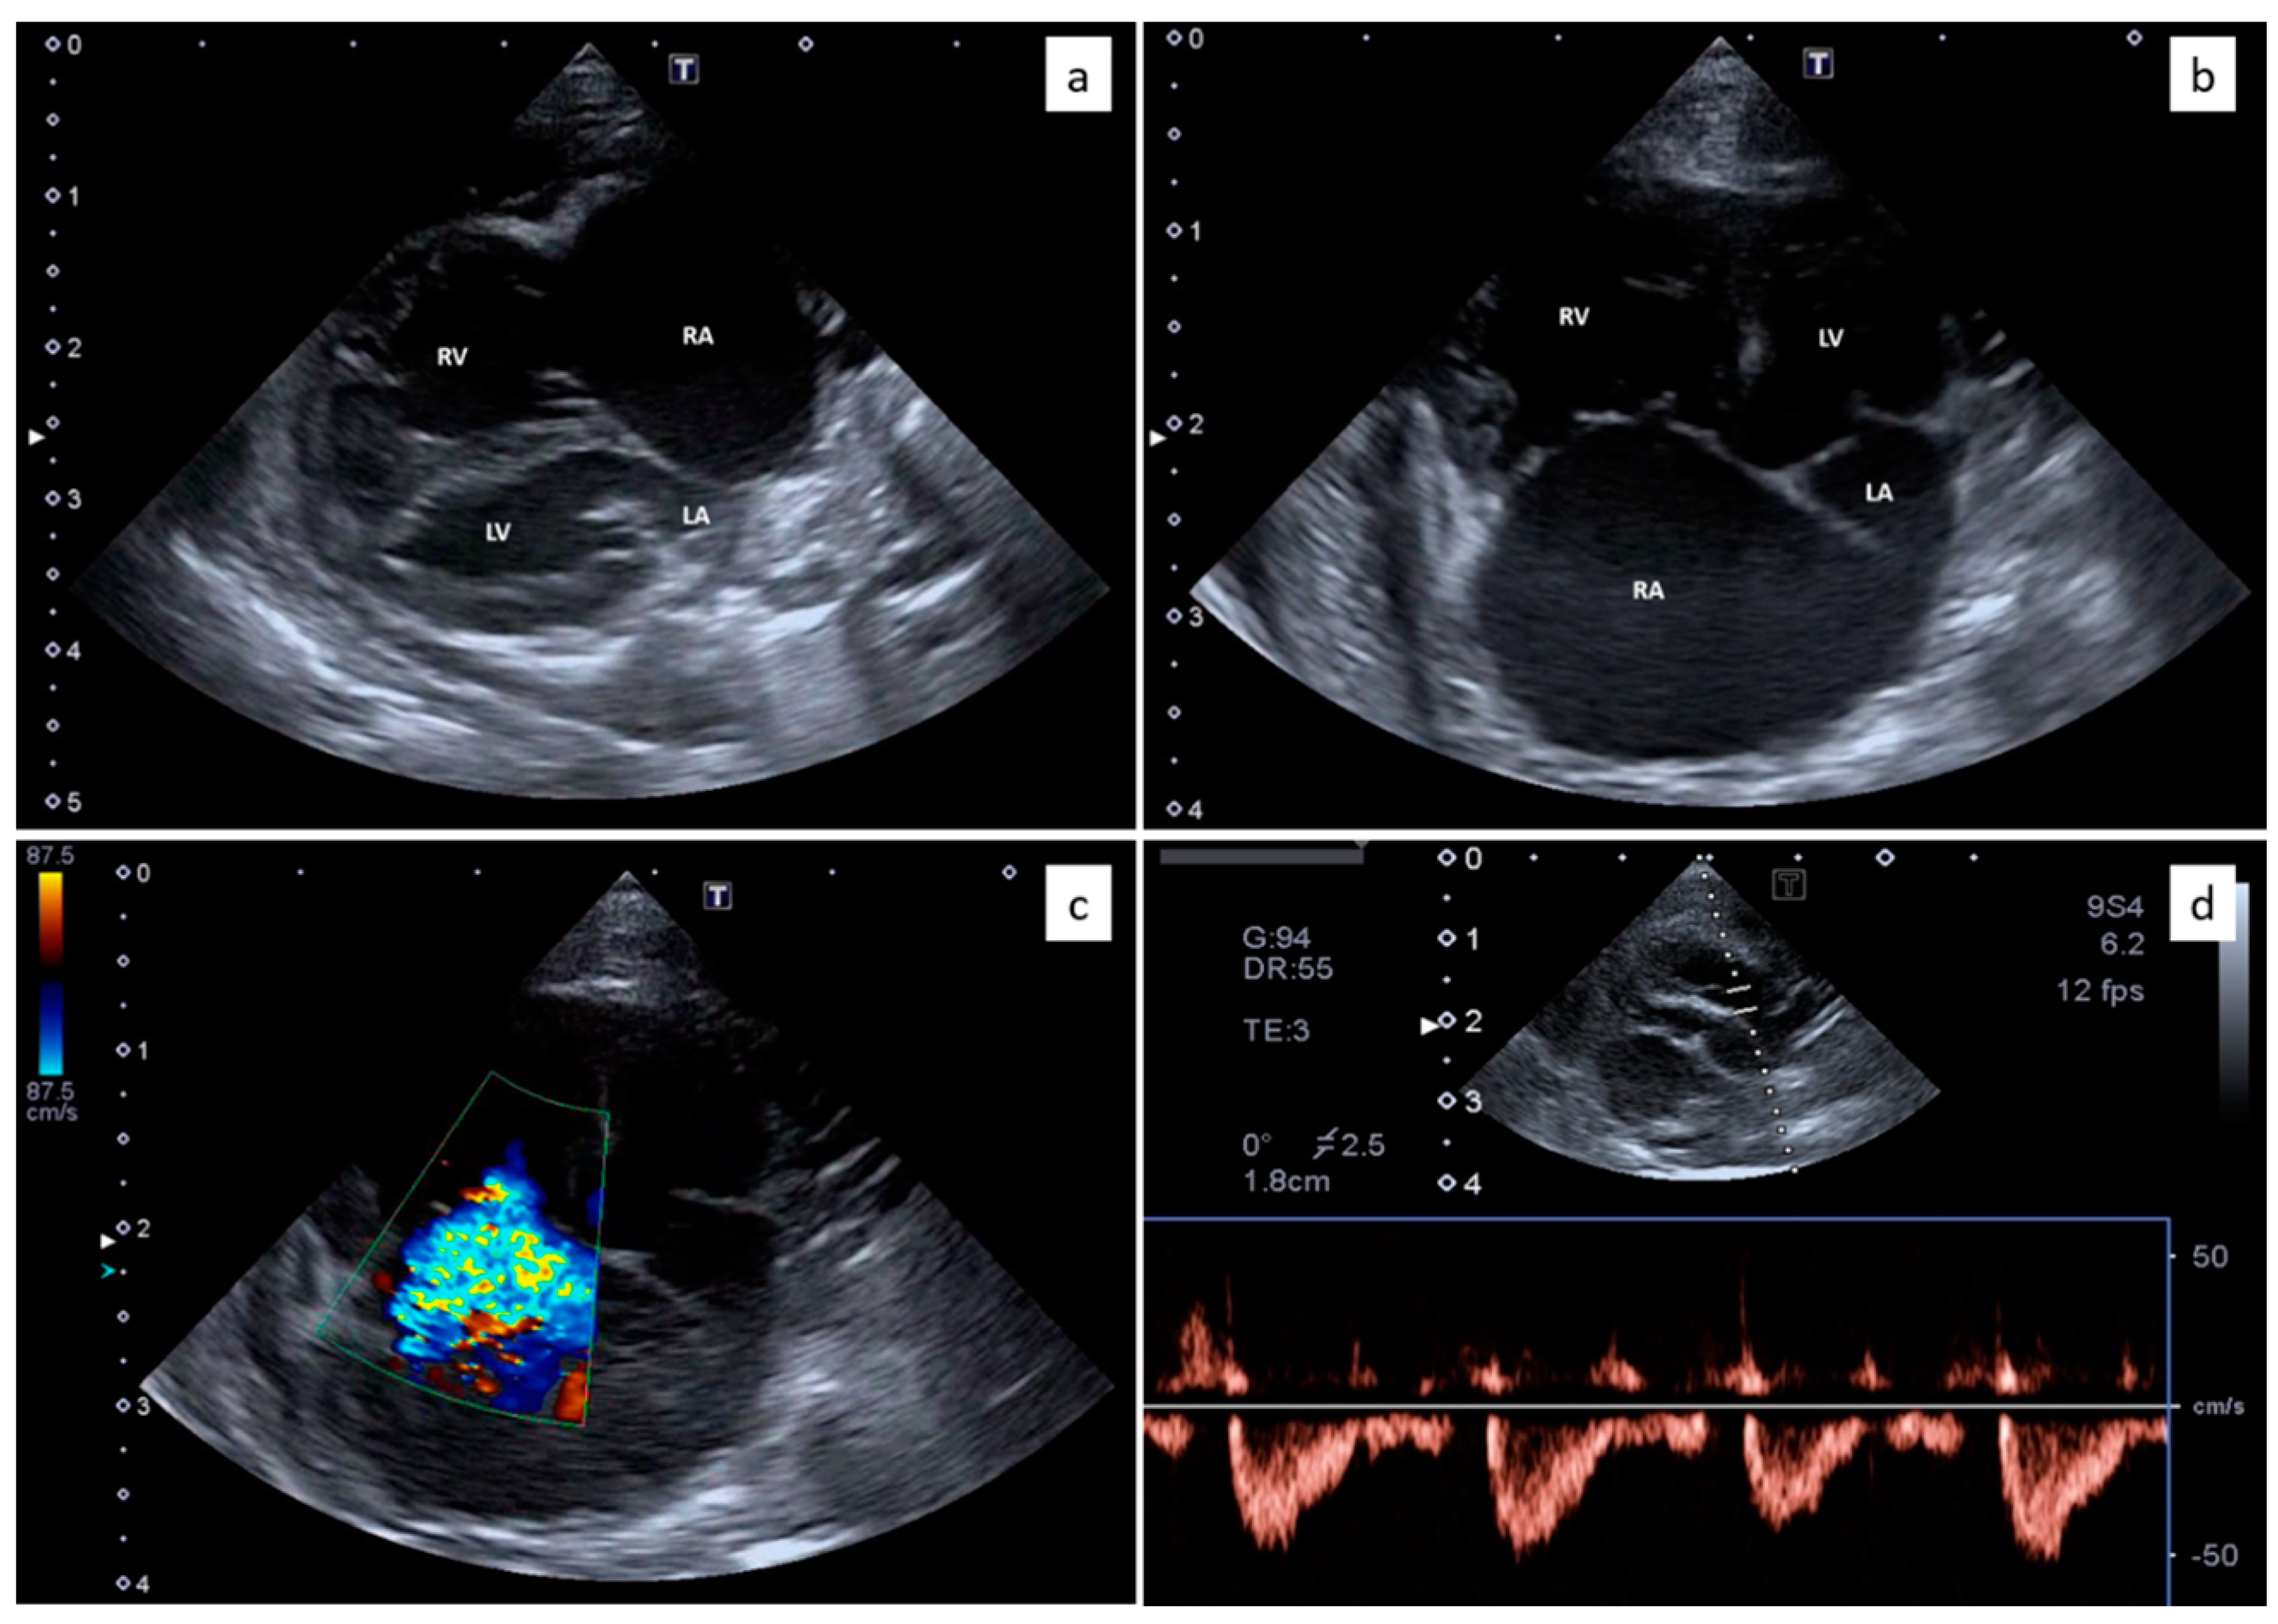

2.2. Thoracic Radiology and Echocardiography